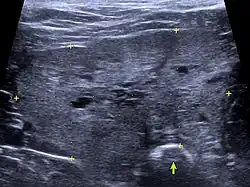

Ultraschallbild einer Kotanschoppung infolge einer Prostatavergrößerung

Ultraschallbild einer vergrößerten Prostata mit nach dorsal gedrängtem Mastdarm (Pfeil) und kleinen Zysten

Erste klinische Anzeichen sind ein wässrig-blutiger Ausfluss aus der Harnröhrenmündung. Wenn das Prostatasekret rückwärts in die Harnblase gelangt, können auch blutige Beimengungen im Urin auftreten. Im Zuge der zentripetalen Prostatavergrößerung drückt diese zunehmend auf den Mastdarm, so dass der Kotabsatz erschwert ist (Dyschezie, Koprostase). Durch den erhöhten Bauchinnendruck beim Kotabsatz kann es zur Entstehung von Perinealhernien kommen. Eine Kompression der Harnröhre ist dagegen, im Gegensatz zum Mann, eher selten. Lediglich in gut einem Viertel der Fälle treten Harnabsatzstörungen wie Dysurie oder Strangurie auf.

Klinisches Bild und die die Rektaluntersuchung der Prostata sind bereits stark hinweisend auf die BPH. Die Prostata ist in der Regel symmetrisch vergrößert und die mediane Furche zwischen den beiden Lappen des Prostatakörpers bleibt erhalten. Weitere Befunde liefert die Sonografie. Die Drüse ist vergrößert, das Parenchym gleichmäßig echoreich (hyperechogen). Gelegentlich treten Prostatazysten auf, die sich als runde, dünnwandige anechogene Gebilde darstellen. Röntgenologisch kann die Größe der Prostata bestimmt werden, gegebenenfalls auch Verkalkungen oder Lymphknotenvergrößerungen. Differentialdiagnostisch sind vor allem die akute und die chronische Prostatitis in Betracht zu ziehen. Diese Erkrankungen lassen sich mit den derzeitigen Methoden nicht sicher von der BPH abgrenzen. Weiterführende Untersuchungsmöglichkeiten sind Elastographie, Computertomographie (insbesondere mit Kontrastmittel) und Magnetresonanztomographie. Diese Untersuchungen sind jedoch nur in Tierkliniken möglich, erfordern eine Vollnarkose und sollten daher vor allem bei Verdacht auf Prostatakrebs durchgeführt werden.